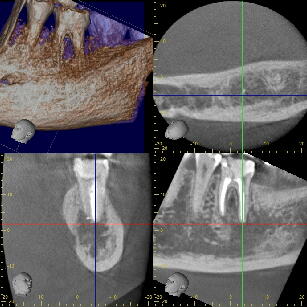

(2)初見では抜歯もしくは遠心根を抜去(ヘミセクション)を考慮しましたが、20代前半で

まだ若いため、約1年半をかけて根の治療を行いました。 ![]() ![]() ![]()

パノラマ画像:黒く写っている病巣が徐々に小さくなっていく様子が分かります。

![]() ![]()

CT画像:当初病巣の下底は下顎管付近まで、また頬側の皮質骨にも穴が開いています

が、徐々に黒い病巣部分が小さくなってきている様子が分かります。 2.再植を応用した根の治療